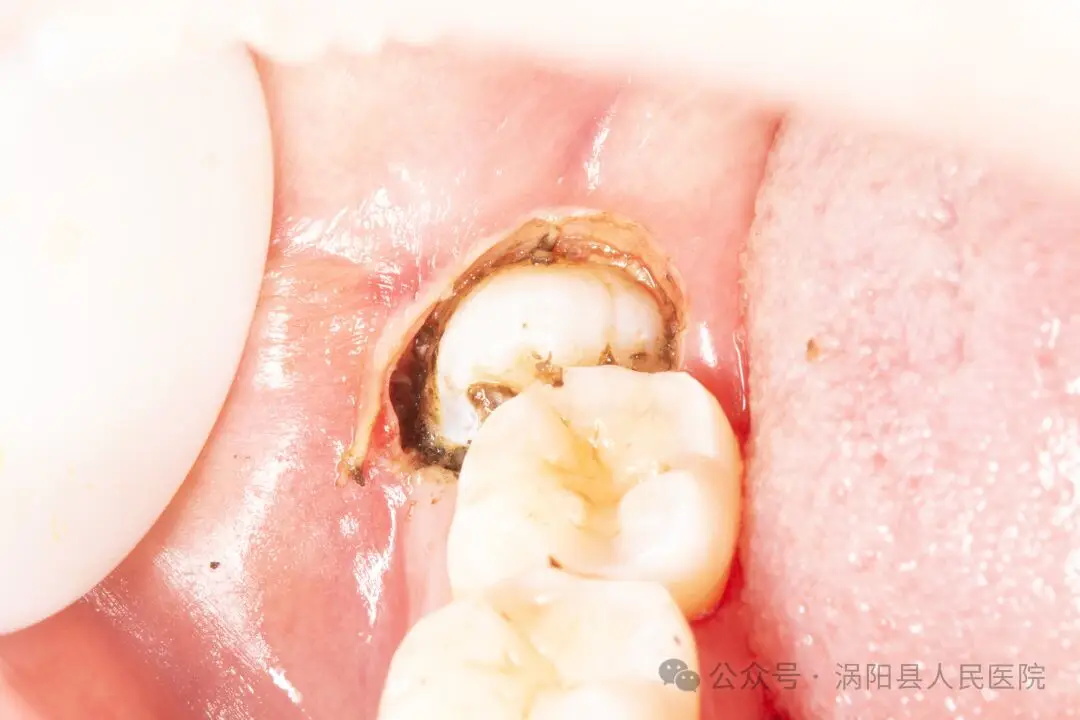

(使用电刀将牙冠周围的软组织气化,相较于传统的切开翻瓣更快、更精准,出血和术后反应也更轻)